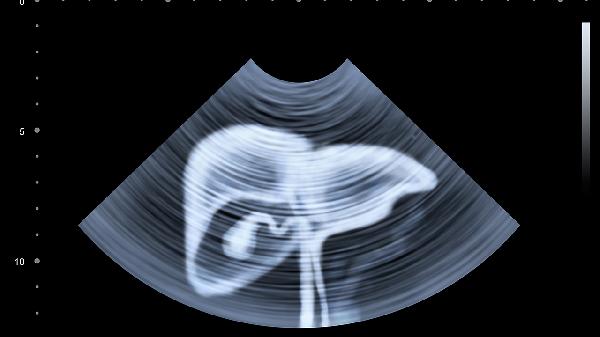

先天性胆管发育异常或创伤后形成,超声显示单房无回声区。体积较大时可压迫肝脏被膜引发钝痛,可能伴随消化不良。无症状小囊肿定期观察,超过5厘米需穿刺硬化或腹腔镜去顶术。

肾小管憩室扩张形成,CT可见圆形低密度灶。多囊肾患者常伴高血压和肾功能异常,单纯性囊肿偶发腰酸。Bosniak分级Ⅰ-Ⅱ类随访监测,Ⅲ类以上需手术探查。